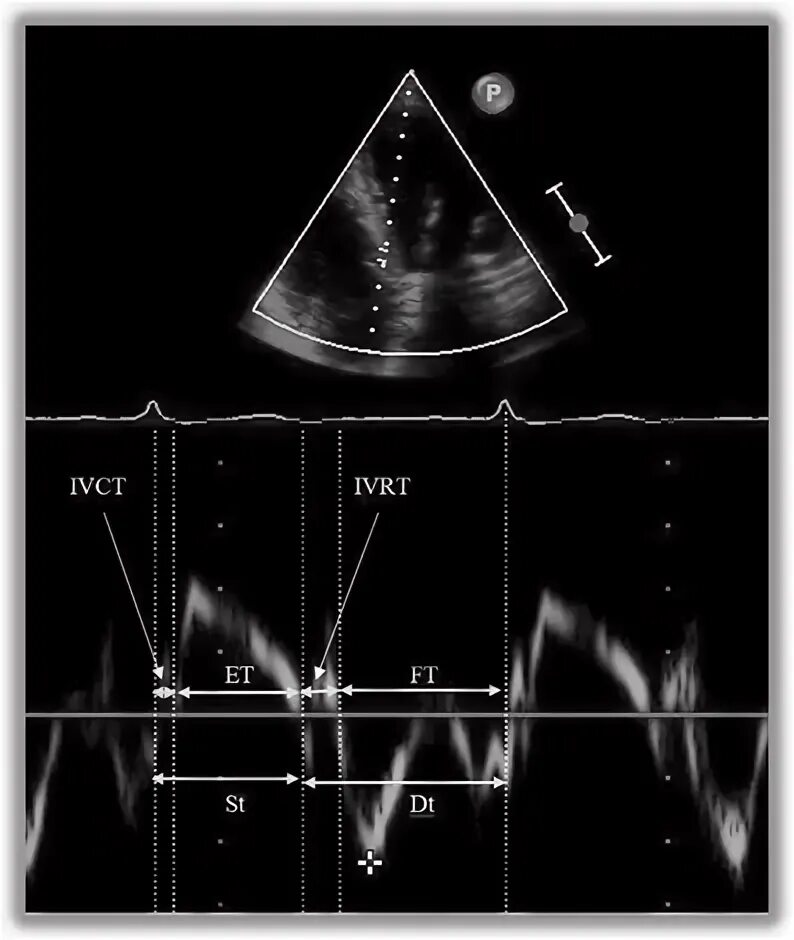

Ддлж по 1 типу по узи сердца